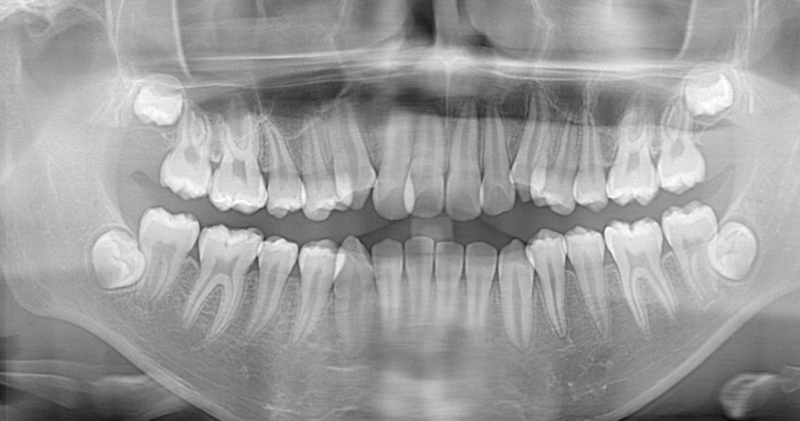

Il momento ideale è tra i 17 e i 25 anni, quando le radici non sono ancora completamente formate e l’osso è più elastico, rendendo l’intervento generalmente più semplice e con un recupero più rapido. Tuttavia, non esiste un’età fissa: la decisione dipende dal posizionamento del dente, dalla presenza di sintomi e da eventuali danni ai denti vicini. Una visita con ortopanoramica consente al dentista di valutare la situazione in modo personalizzato.